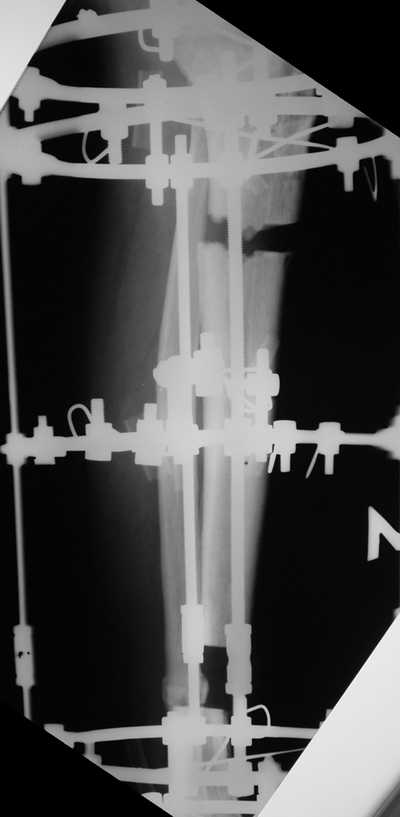

Male 54 years old, diabetic, blind in both eyes, with infected (MRSA) non union distal tibia after fracture 8 month ago. In acute phase treated by ORIF with LCP tibia and fibula. Treatment complicated by infection and after 6 month hardware was removed and treatment continued by cast fixation. You can see malposition of fragments In this stage beginning treated by Ilizarov fixation with use Hexapod system, allows anatomical position of fragments and you see signs of union.

Sorry, I wiil tray now pictures of my case.